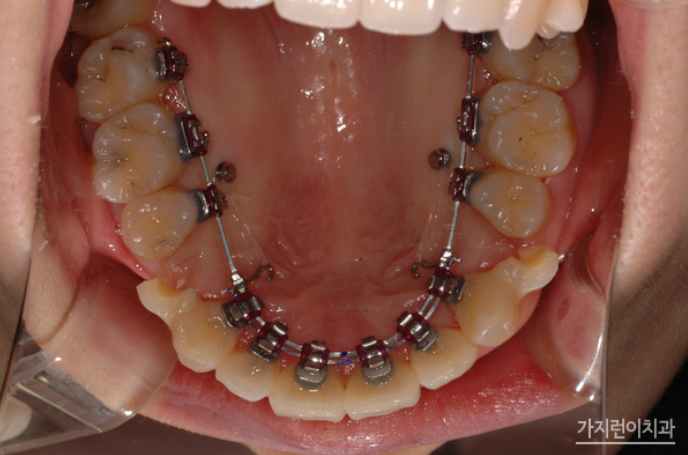

위 사진은 더블와이어를 이용한 설측탄댐장치인데요. 치아의 비뚤어짐이나 쓰러짐, 뿌리 조절 등을 정교하게 컨트롤할 수 있는 교정장치입니다. 3차원적인 치아이동 조절을 위해 특수하게 고안된 장치인데요. 기존의 설측교정장치가 뿌리 이동이 용이하지 않았다는 단점을 개선해 미세한 조절이 가능해졌다는 특징이 있습니다.

위 사진처럼 설측으로는 복잡해보이는 장치가 보이지만 이를 앙 다문 상태에서는 장치가 보이지 않는데요. 두 개의 와이어를 사용해 치아이동에 필요한 힘을 효과적으로 줄 수 있는데다 치아의 쓰러짐을 방지해 마찰력을 줄여 결과적으로는 치료기간이 크게 단축되었다는 것을 볼 수 있습니다. 게다가 덧니, 돌출입, 비발치 교정 등 기존 설측교정장치보다 빠르고 탁월한 결과를 얻어볼 수 있겠습니다.